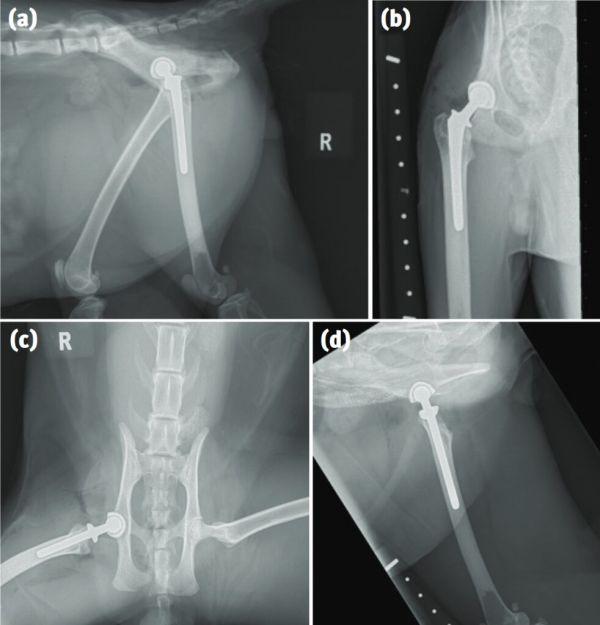

关节镜冲洗术可用于已经出现关节炎的关节。然而,猫关节的尺寸比关节镜的尺寸小,可能会因插入关节镜导致损伤。因此,这种方法的获益可能有限。在药物治疗和环境改造无效的终末期OA中,可以通过关节融合、置换或切除进行挽救手术(图11)。如果只有一个关节受到影响,那么手术可能是治愈性的。如果问题较为广泛,一些患者在手术后仍需要营养和药物治疗。

图11. 全髋关节置换术是治疗猫髋关节OA的一种选择。(a)侧视图。(b)一侧骨盆。(c)骨盆腹背视图。(d)股骨内外侧视图。